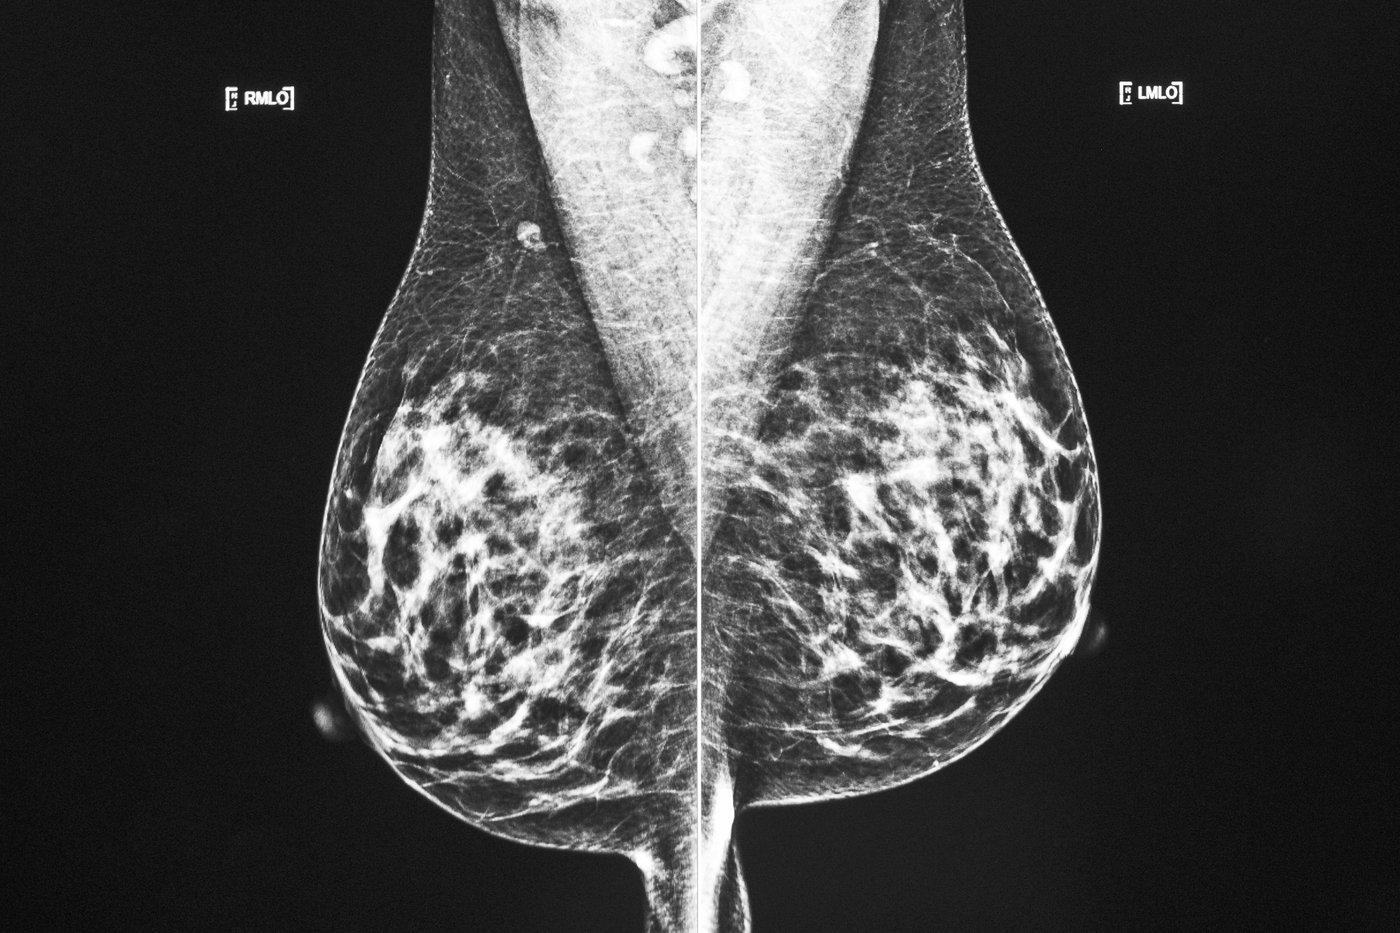

Les médecins réalisent aujourd'hui que certains de leurs traitements étaient inutilement agressifs, a dit le docteur Veillette, qui cite en exemple l'époque où une intervention pour un cancer du sein impliquait l'ablation du sein, des ganglions et même du muscle dans la paroi thoracique.

«Il y avait beaucoup de complications pour les femmes, a-t-il dit. Et aujourd'hui on se rend compte que ce type de traitement-là était beaucoup trop agressif.»